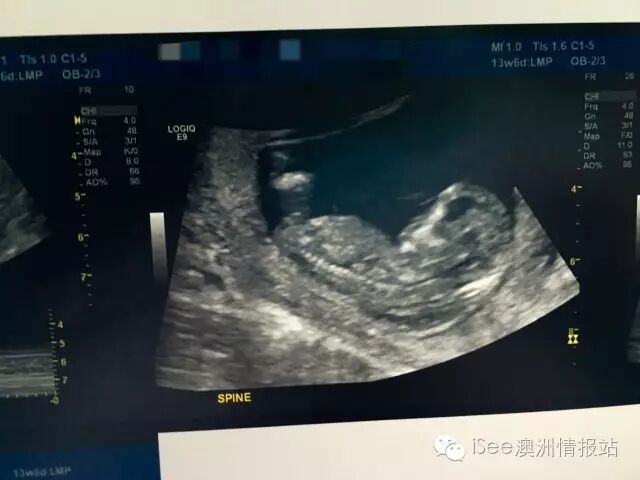

第二次B超,也叫唐氏综合

这是我13周做唐氏综合时候他的样子。真是吓了一条!因为一个多月前他还是一个小球呀,怎么现在已经长成人形了。后来看到文章据说前三个月是胎儿细胞分裂最快的时期,如果整个孕期都按这个速度分裂的话,你到最后会孕育一只大象…:)

关于费用,唐氏综合应该也是孕期最贵的一个检查项目了。我做的是150刀,而且这个项目医保卡是不能报销的。妈妈群里还有做了400-600刀的,所以每个做B超的地方收费都不一样你打电话预约的时候就要问清楚。